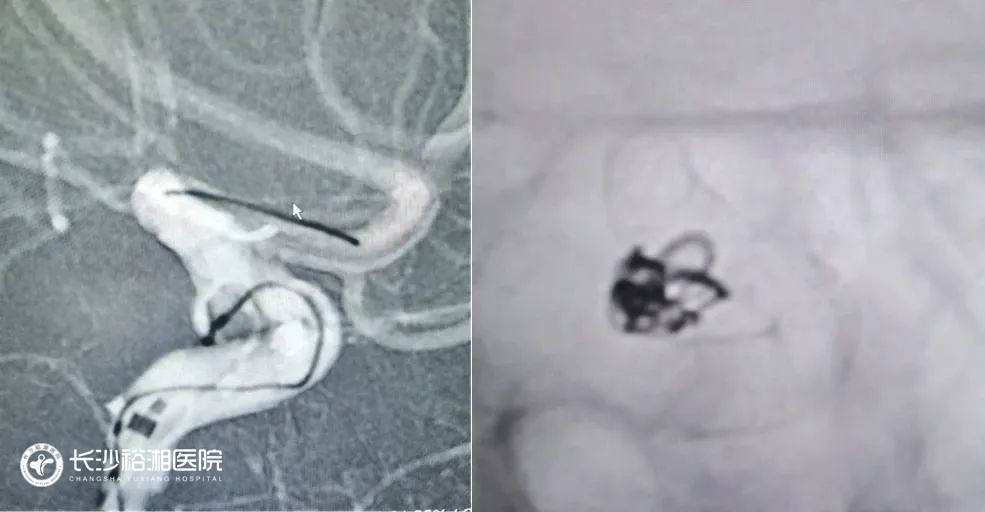

血管內(nèi)介入栓塞術(shù)無需開顱,通過人體血管天然通道實(shí)現(xiàn)對(duì)動(dòng)脈瘤的治愈性栓塞,是一種安全有效的微創(chuàng)手術(shù)方法。隨著栓塞材料和治療理念的不斷進(jìn)步,目前介入栓塞適用于絕大部分顱內(nèi)動(dòng)脈瘤,尤其是巨大動(dòng)脈瘤、夾層動(dòng)脈瘤、頸眼動(dòng)脈瘤、椎基底動(dòng)脈瘤和血泡樣動(dòng)脈瘤等復(fù)雜動(dòng)脈瘤的治療。我院擁有省內(nèi)先進(jìn)的腦血管病復(fù)合手術(shù)室,神經(jīng)外科腦血管病治療團(tuán)隊(duì)具有熟練扎實(shí)的手術(shù)技巧,在復(fù)雜顱內(nèi)動(dòng)脈瘤的介入栓塞和外科治療方面經(jīng)驗(yàn)豐富。

(血流導(dǎo)向裝置置入)

(血流導(dǎo)向裝置示意圖)